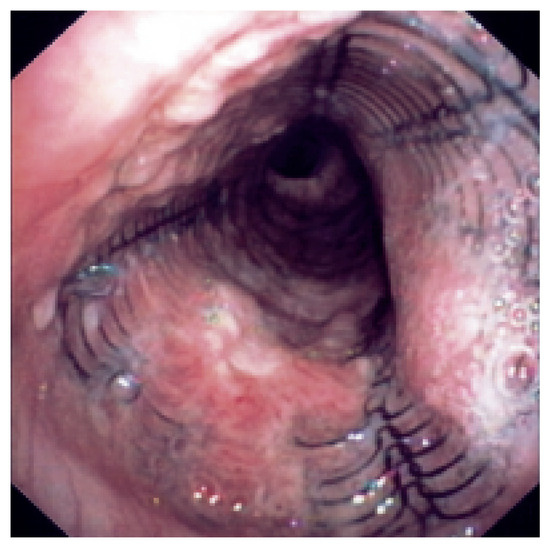

Endobronchiales Stenting

Patients with lung cancer often have bulky endobronchial disease, endobronchial extension, or airway compression. Many endobronchial treatment modalities are available to supplement traditional therapies for advanced lung cancer. Since the early 1980s, technical advances in interventional techniques have enhanced symptom-free survival and quality [...] Read more.

Patients with lung cancer often have bulky endobronchial disease, endobronchial extension, or airway compression. Many endobronchial treatment modalities are available to supplement traditional therapies for advanced lung cancer. Since the early 1980s, technical advances in interventional techniques have enhanced symptom-free survival and quality of life for patients with lung cancer. Although interventional procedures are not definitive therapies, they often relieve the strangling sensation produced by airway occlusion. For patients with respiratory symptoms associated with their disease, the stent placement provides symptom palliation and improves quality of life. The author reviews the use of several available endobronchial stents. Full article